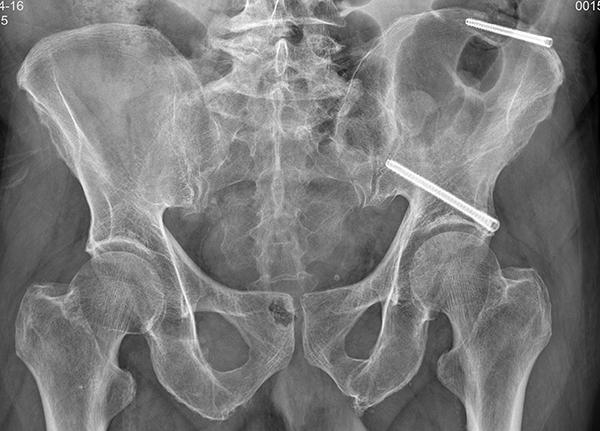

手术前,团队通过三维CT扫描获取骨盆精准影像,在电脑上规划出最佳的螺钉置入路径。骨科手术机器人接收指令后,机械臂精确定位,仅通过两个硬币大小的微创切口(约1.5厘米),在实时引导下顺利完成了髂骨螺钉及LC‑Ⅱ螺钉的置入。整个手术不到2小时,出血量仅约10毫升。

术后换药时,兰老先生看着身上两个小小的切口,反复确认:“这就把那么长的钉子打进去了?就能做完手术了?”他坦言:“刀口很小,基本没什么太痛的感觉。”更令他惊喜的是,术后第二天,他就在医务人员指导下开始了康复训练。“原本以为要躺好几个月,没想到现在就能慢慢活动了。”